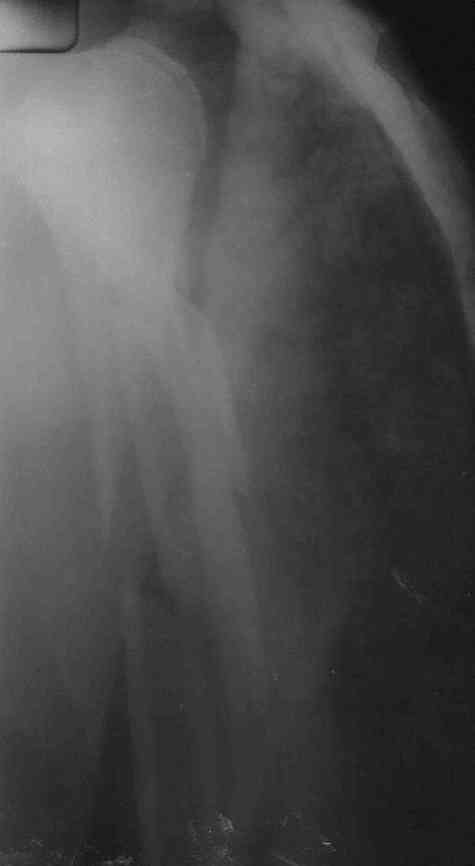

Многооскольчатый перелом плечевой кости в В/3

Ув. коллеги, со стационара в поликлинику пришла женщина, 48 лет, травма 29.08.07 лечение консервативное в гипсовой повязке.

Оперативное лечение не предлагалось. Обыективно - правая верхняя конечность в гипсовой лангете едва прикрывающей правый плечевой сустав.

Как наиболее правильно поступить?

Может лечить по Сармиенто?

Или исправить повязку до здоровой лопатки на 2-3 недели с заменой на Сармиенто?